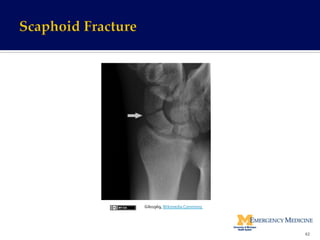

¡  Scaphoid Fracture!

§  Most common carpal bone fracture!

§  Mechanism = fall on outstretched hand or axial load to thumb!

§  2/3 of fracture in waist of scaphoid!

§  Imaging – Initial x-rays may fail to demonstrate fracture !

▪  > 10% of cases!

▪  Repeat Imaging in 2 weeks will often show fracture!

§  Clinical findings = tenderness in anatomical snuff box!

§  Treatment!

▪  Non-displaced or clinically suspected fracture !

▪  Thumb spica Splint!

▪  Displaced fractures will require ORIF!

▪  Complications !

▪  Avascular necrosis of proximal fragment -> arthritis!

▪  Delayed union or malunion!